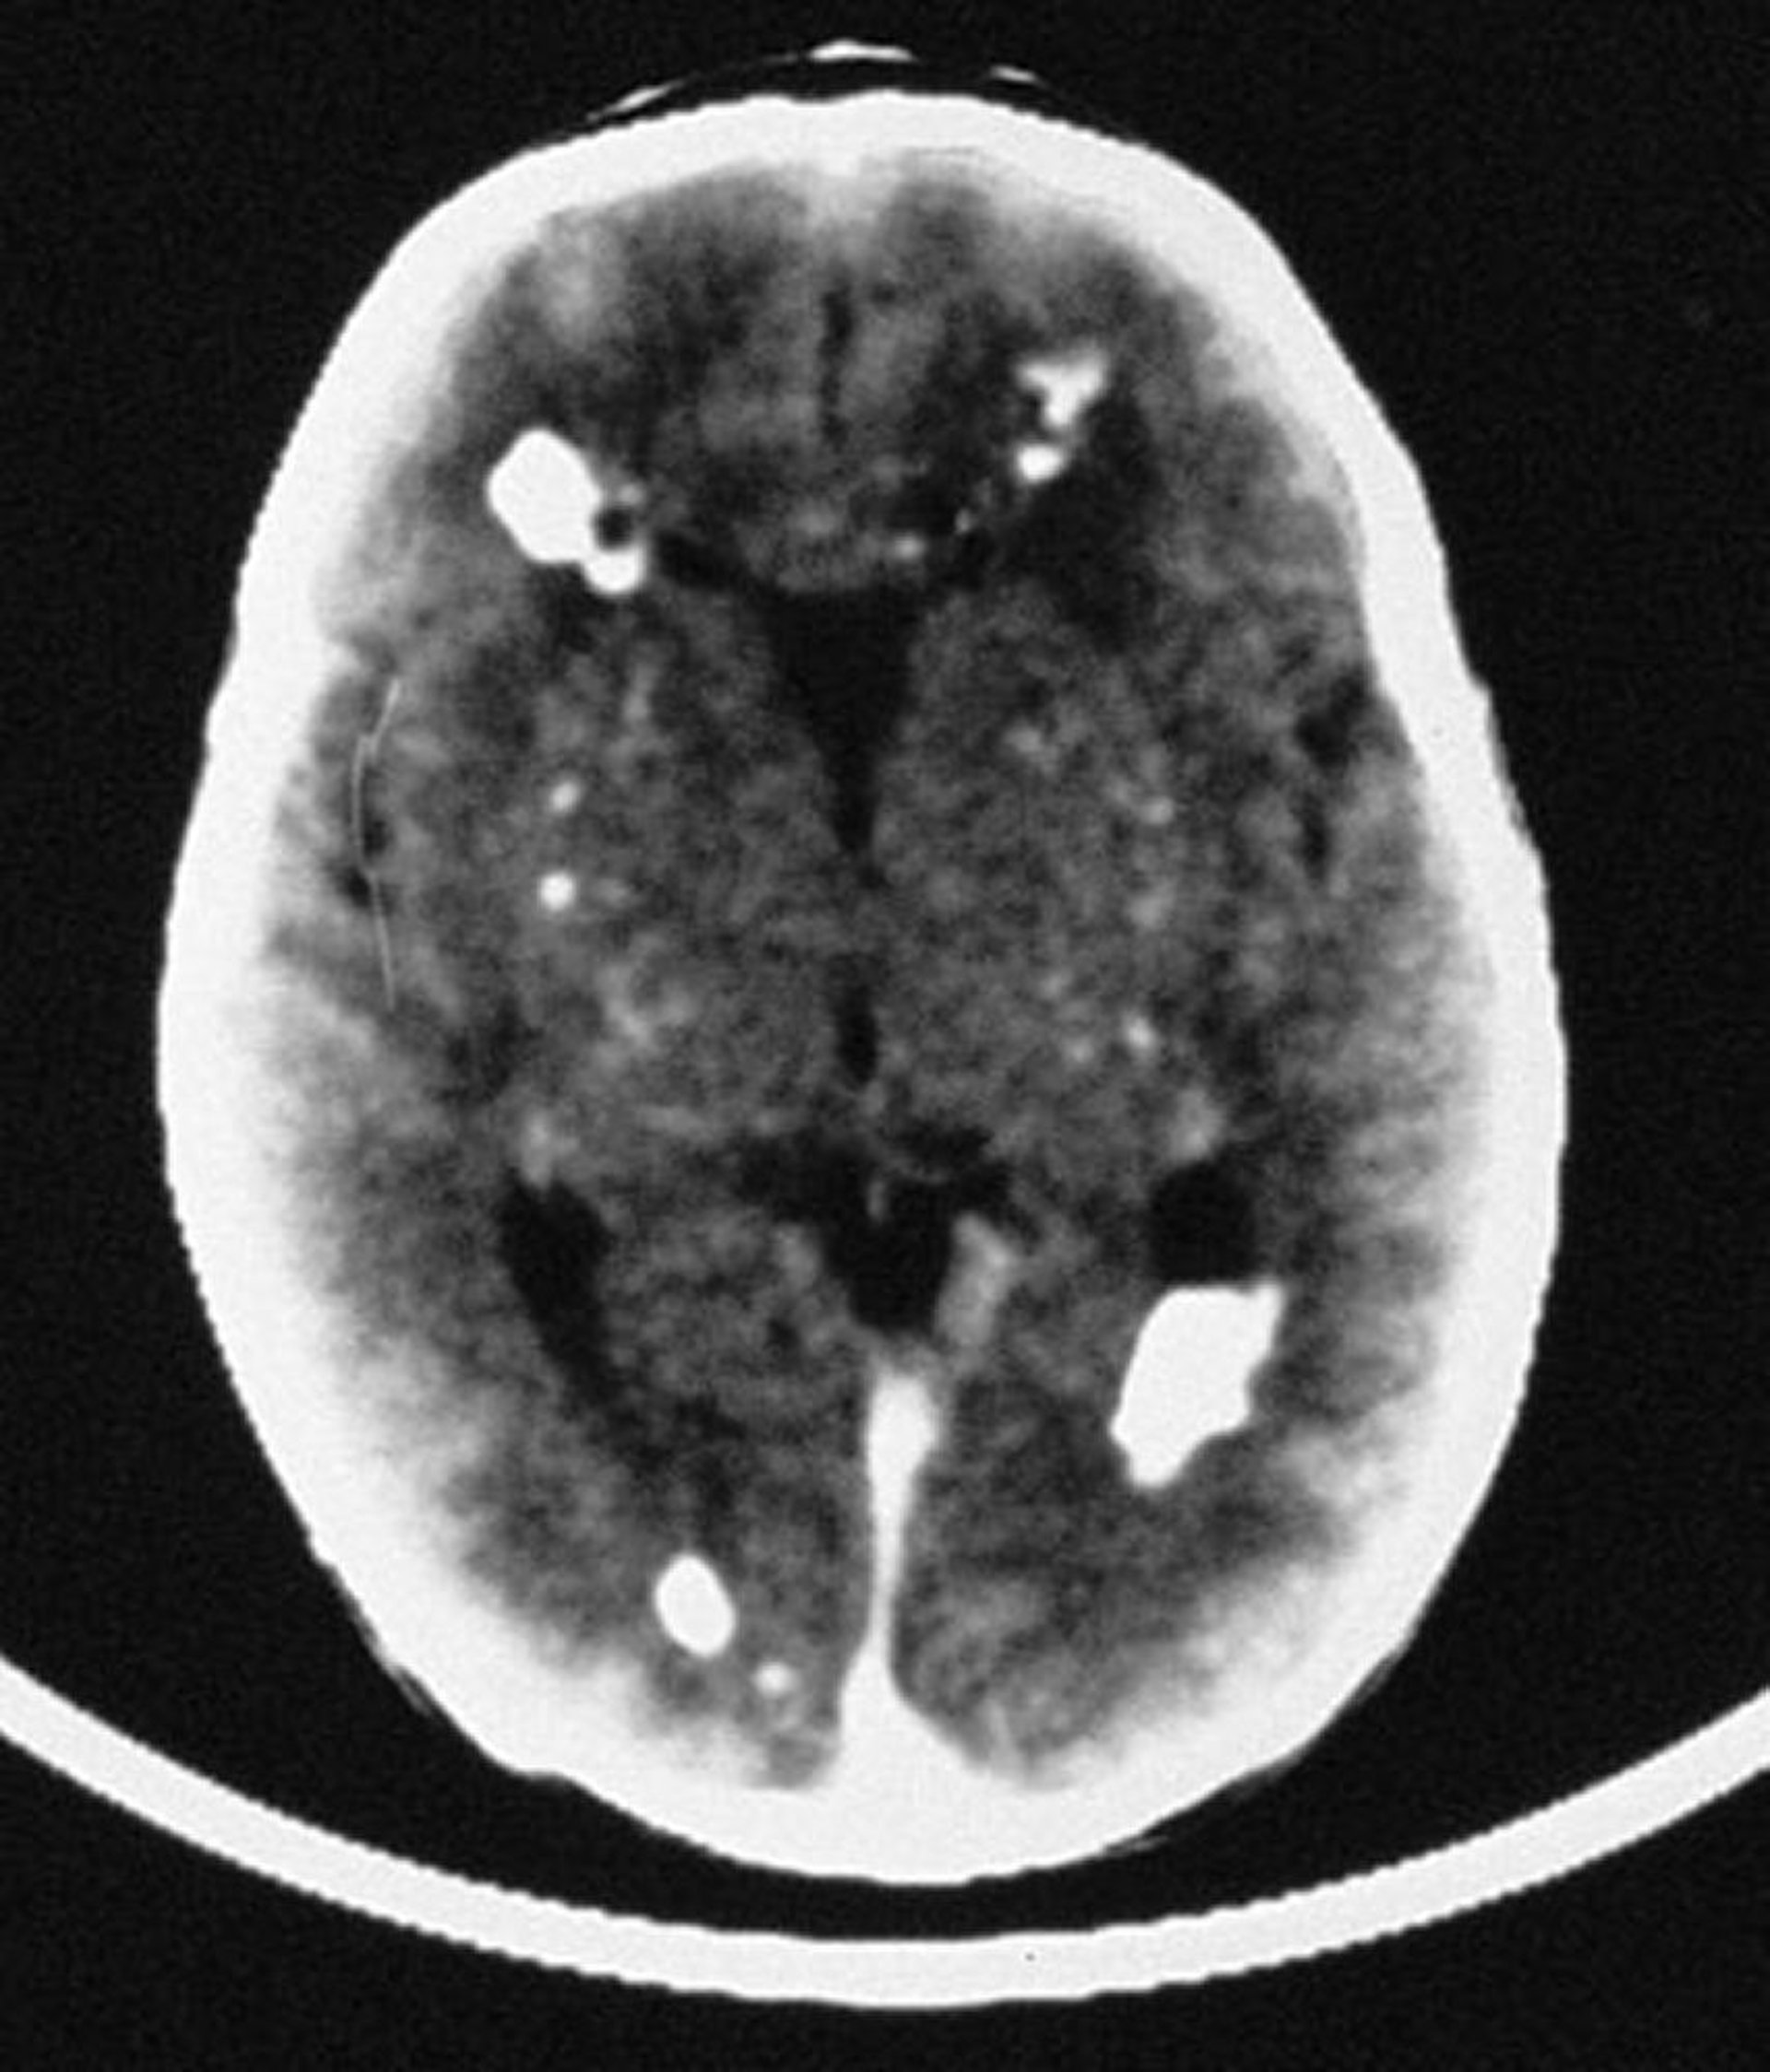

Врожденная цитомегаловирусная инфекция

Как видно на этом рисунке, КТ выявляет множественные внутричерепные участки кальцификации, в основном перивентрикулярные по расположению, но также вовлекающие сосудистые структуры головного мозга.

By permission of the publisher. From Demmler G: Congenital and perinatal infections. In Atlas of Infectious Diseases: Pediatric Infectious Diseases. Edited by CM Wilfert. Philadelphia, Current Medicine, 1998.